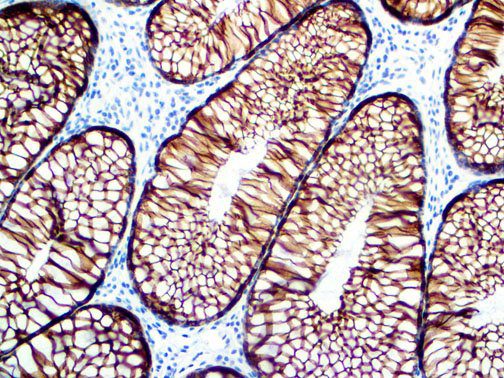

The first cytokines released are interleukin 1β (IL-1β) and tumor necrosis factor-α (TNF-α), which attract a variety of circulating white blood cells (WBCs) to the infection site, including neutrophils, monocytes, macrophages, and natural killer (NK) cells. This response, along with the antipathogenic chemicals released by these cells (i.e., complement), comprise the innate immune response. These cells directly attack the invading pathogen and also release additional cytokines, chief among them interleukin-1 and 6 (IL-6). IL-6 is essential for invoking the adaptive immune response, which calls T-cells, B-cells, and T helper (Th) cells to the infection site. IL-6 also stimulates further recruitment, proliferation and activation of macrophages.

It is the ICU physician who is most likely to witness one of the deadliest manifestations of the abnormal immunological response, the cytokine storm syndrome (CSS). This response is also referred to by some as the cytokine release syndrome (CRS). CSS is characterized by continuous activation and expansion of macrophage and lymphocyte populations, which secrete large amounts of cytokines, causing the cytokine storm. This massive cytokine release is akin to hemophagocytic lymphohistiocytosis (HLH) disease, a syndrome characterized by initial unchecked and persistent activation of cytotoxic T lymphocytes and NK cells.